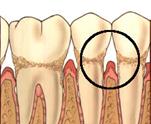

În ultimii 25 de ani s-au înregistrat progrese remarcabile în tratamentul parodontopatiilor marginale mai ales în zona regenerarii parodontale si osoase, teorie sustinuta de ipoteza conform careia celulele progenitoare din ligamentele parodontale sunt capabile sa regenereze sistemul ligamentar de sustinere parodontala (Melcher - 1976).

Majoritatea tratamentelor care aveau la baza aceasta ipoteza foloseau membrane-bariera pentru regenerarea tisulara dirijata (guided tissue regeneration - GTR) cu rol de a selecta si spori anumite populatii celulare si de a stimula apozitia coronara de ligamente si de cement pe suprafetele radiculare denudate. Ulterior, utilizarea grefelor os 24524m1214y oase (autogrefe, alogrefe, xenogrefe) si a conditionarii suprafetei radiculare cu acid citric a adus noi evidente histologice în explicarea procesului de regenerare tisulara. Vindecarea plagilor parodontale dupa aceste procedee este de tipul noii insertii si nu prin regenerare parodontala (vezi tabel).

Refacerea osului alveolar, a ligamentului parodontal si a cementului pe o suprafata radiculara patologica anterior |

Legatura tesutului conjunctiv sau epitelial de o suprafata radiculara ce si-a pierdut aparatul initial de sustinere; poate fi adeziune epiteliala si/sau adaptare conjunctivala si include cement nou |

Refacerea legaturii tesutului epitelial si conjuctiv cu suprafata radiculara si osul alveolar, dupa o incizie sau un traumatism |